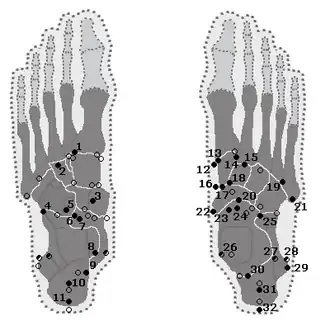

De frequentie van het os trigonum bij gezonde individuen varieert van 2,5 tot 11,4%,[2] alhoewel de spreiding ook wordt geschat tussen 1 en 25%.[3] In een radiologische studie onder 3460 individuen bedroeg de prevalentie 12,7%.[6] Een Turkse studie onder mannen gaf een prevalentie van 4,3%.[7] In een andere studie werd het os trigonum in een selectie van skeletten uit het begin van de 20e eeuw bij 1,7% van de gevallen gevonden. Bij 513 sprongbeenderen van oorspronkelijke bewoners van Amerika en van Eskimo's werd het botje in zijn geheel niet gezien.[8] Ondanks deze uiteenlopende cijfers wordt het os trigonum na het os tibiale externum beschouwd als het vaakst voorkomende accessoire voetwortelbeentje.